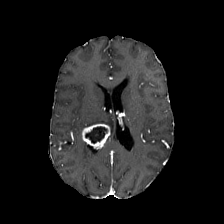

Diffusion models have shown impressive performance for generative modelling of images. In this paper, we present a novel semantic segmentation method based on diffusion models. By modifying the training and sampling scheme, we show that diffusion models can perform lesion segmentation of medical images. To generate an image specific segmentation, we train the model on the ground truth segmentation, and use the image as a prior during training and in every step during the sampling process. With the given stochastic sampling process, we can generate a distribution of segmentation masks. This property allows us to compute pixel-wise uncertainty maps of the segmentation, and allows an implicit ensemble of segmentations that increases the segmentation performance. We evaluate our method on the BRATS2020 dataset for brain tumor segmentation. Compared to state-of-the-art segmentation models, our approach yields good segmentation results and, additionally, detailed uncertainty maps.